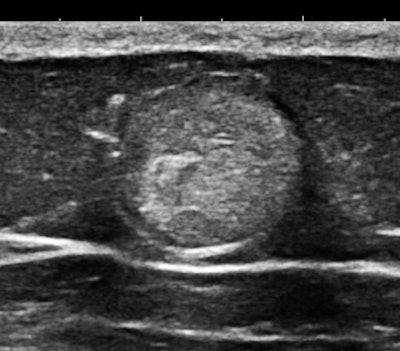

Of course, any of you might say that systemic mastocytosis is such a rare occurrence that one would probably never ever encounter one, but that is probably only true with fully and classically symptomatic cases. We have started looking at abdominal subcutaneous fat as part of our scanning routine, and guess what? This may not be such a rare occurrence at all. Here are some 15-MHz abdominal wall images of a 63-year-old hypothyroid woman who previously had a hysterectomy for a precancerous endometrial polyp:

Her history was interesting, with allergies that began in middle age and episodes of flushing during the past five years that she attributed to "hot flashes."

Some of you might think these nodules look like occasional findings in breast ultrasounds that are commonly thought to be lipomas. Lipomas are encapsulated fat, and they are distinguished from fat mainly by their capsular boundary. Here is another type of echogenic nodule, a solid mass of mixed histology with fat, muscle, and vascular components. This type of mass is typically palpable; their firmness is demonstrated by shear-wave elastography:

The first example is of an infiltrating, multifocal process, such as with leukemia; the second involves stable islands of cells without a supporting macrostructure; and the third is a solid, benign mass. The image features are distinct.